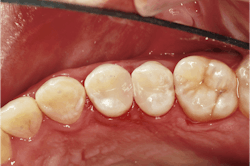

Once the restoration is finished, the rubber dam is removed and the occlusion is checked. Finally, a quick polish is done with a single-step polishing system, the Optragloss. At this point, we have created a great interproximal contact for Lee and restorations that should last very well while we continue to restore his other carious lesions (figure 13).

A post-op bitewing radiograph shows successful restorations for Lee (figure 14).